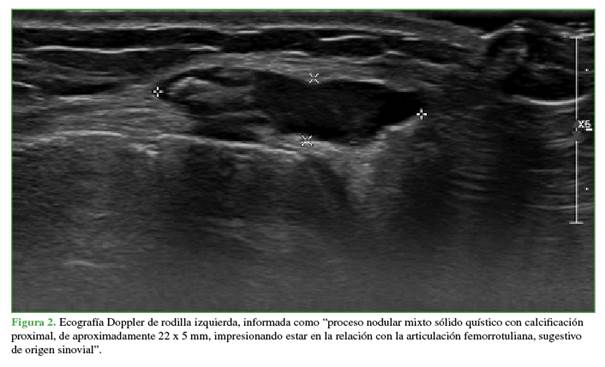

En ese momento, se solicitó el par radiográfico correspondiente, una ecografía Doppler y una RM. La radiografía no mostró particularidades. En la ecografía, la lesión fue informada como un “proceso nodular mixto sólido quístico con calcificación proximal, de aproximadamente 22 x 5 mm, impresionando estar en la relación con la articulación femororotuliana, sugestivo de origen sinovial” (Figura 2). En la RM, se visualizó la misma imagen ya descrita, pero ahora de 16 x 18 x 21 mm, también hiperintensa en las secuencias T1 y T2 (Figura 3).